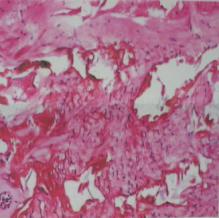

术后切除组织病理报告:瘢痕肉芽组织(图5)。

图5:术后病理:瘢痕肉芽组织